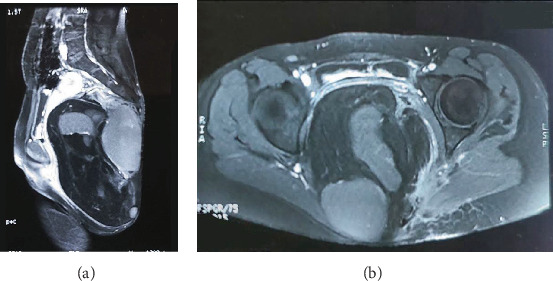

Sacrococcygeal teratomas are rare in adults, despite being common in infants. Adult presentations are often asymptomatic and may go undetected until complications arise. We report a case of a 20-year-old female with a long-standing sacral swelling. Imaging revealed a large, well-circumscribed mixed solid-cystic mass in the presacral region causing displacement of pelvic structures. Surgical excision of the tumor was done along with the surrounding rectal wall. Early surgical intervention is essential to prevent malignant transformation and optimize outcomes.